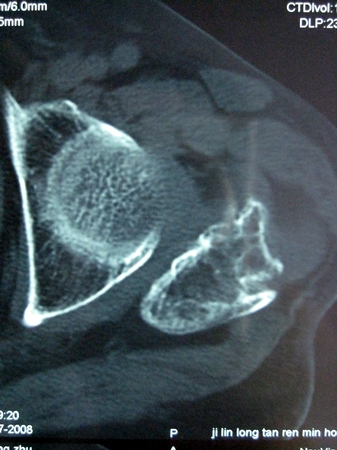

以下是引用lkc8963在2008-12-19 21:19:00的发言:[br]左?右?患侧大转子上移,股骨颈骨质浓杂,髋周见多发条片状骨化影,以小转子为著,多为陈旧性股骨颈骨折后改变并骨化性肌炎.请咨询既往史!